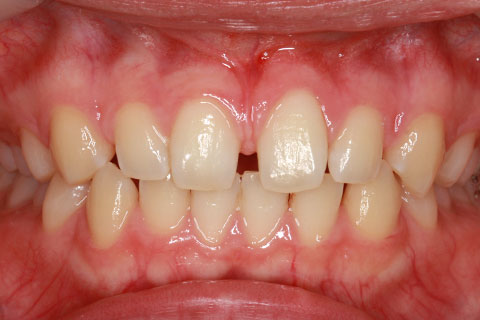

オールセラミックの症例2

- 年齢・性別

- 45歳男性

- 治療期間

- 2ヶ月

- 抜歯

- なし

- 治療費

- 70.4万円

- 備考

- 前歯8本の歯列不正によるセラミック治療

- 治療内容

- 歯質を削除し、セラミック冠をセメント合着

- 施術の副作用(リスク)

- 知覚過敏、歯髄炎、荷重負担